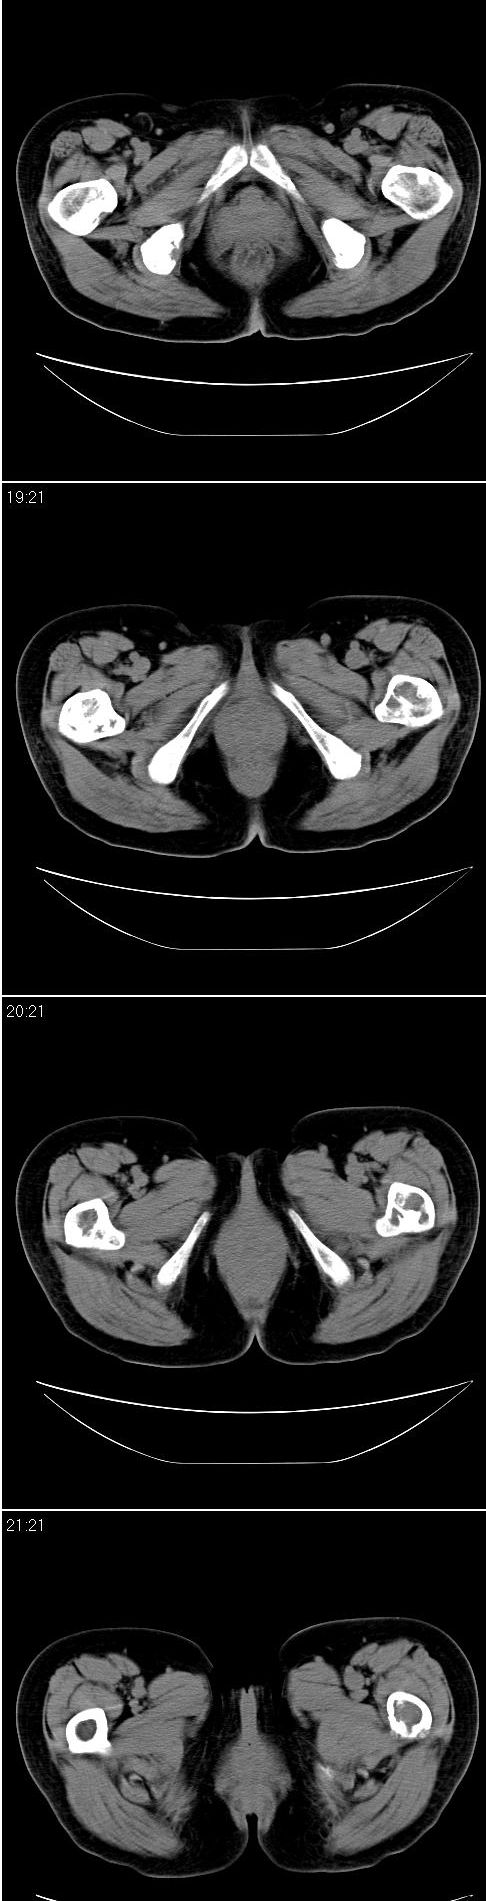

标题: CT13121:女,54岁。乳腺癌术后8年。 [打印本页]

女,54岁。乳腺癌术后8年。现感觉左腿酸困不适,并向下放散。左腿僵硬,不由自主。

典型溶骨型转移瘤。

骨盆及腰椎多发性溶骨性转移瘤.

成骨及融骨转移。

结合病史考虑乳腺癌术后多骨骨转移。

患者臀部皮下脂肪、筋膜、臀大肌处多个小结节、钙化影,看来挨了不少肌肉注射的苦头

支持 骨转移瘤---混合型以溶骨为主

结合临床考虑多骨多灶性溶、成骨性转移。